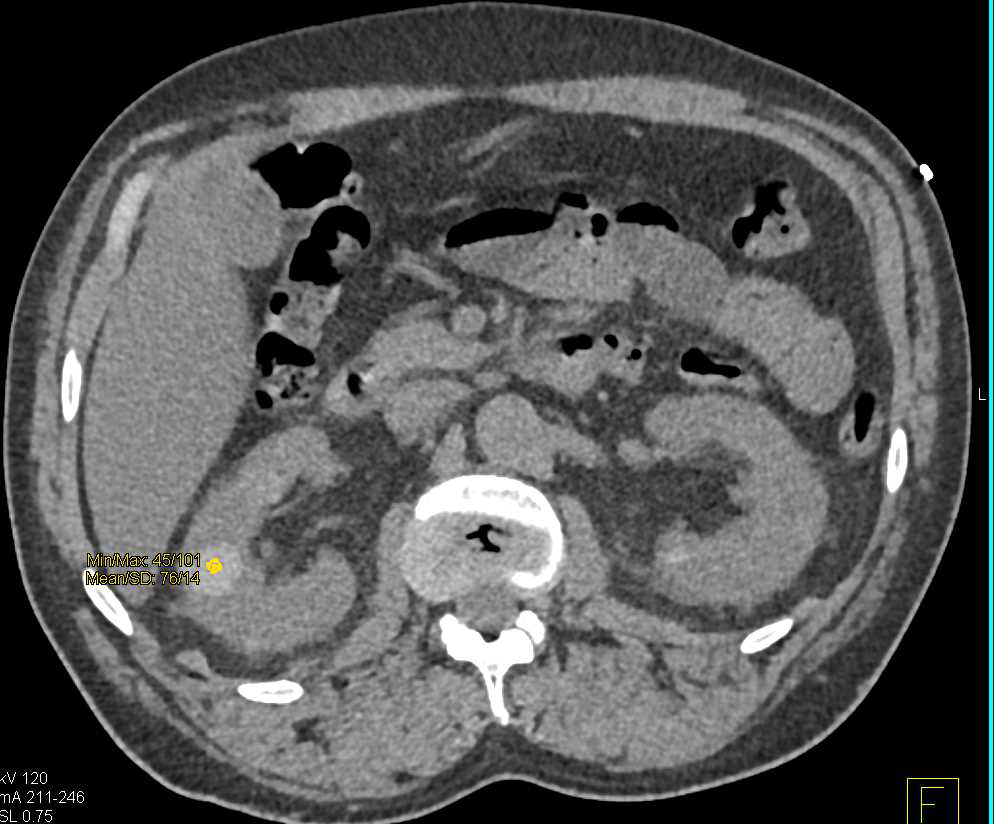

Pseudoaneurysm Left Kidney Due to Partial Nephrectomy